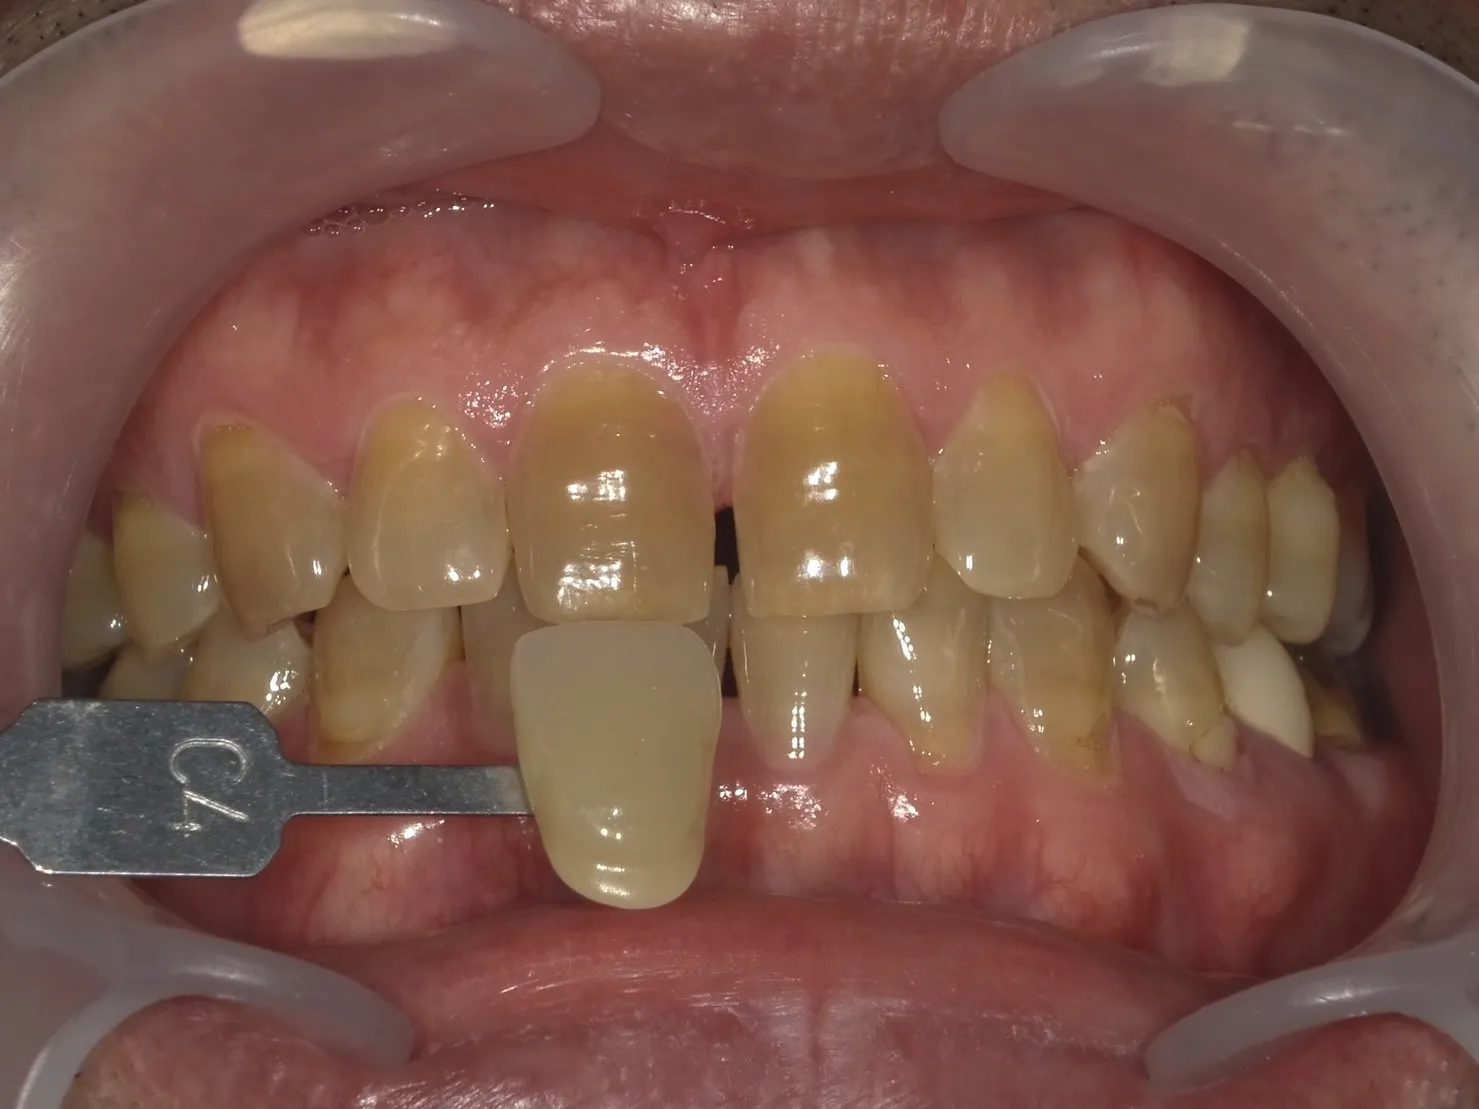

テトラサイクリン歯の治療法

テトラサイクリン歯の治療には、以下の方法が一般的に用いられます。

| メリット | デメリット | |

| ラミネートベニア | 自然な見た目を実現可 耐久性が高い 着色や変色に強い |

歯の表面を削る必要がある 修復が難しい場合がある コストが高い |

| ダイレクトボンディング | 治療時間が短い 比較的低コスト 歯の削除が少ない |

耐久性に劣る 時間が経つと変色する可能性がある |

| ホワイトニング | 非侵襲的で歯を削る必要がない 全体的に白くできる |

テトラサイクリン歯による深い着色には限界がある |